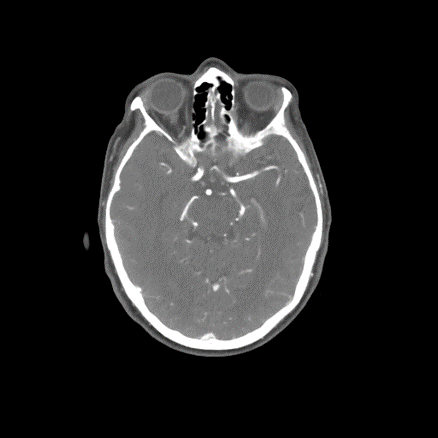

3/ On arrival, NIHSS now 3 for R drift, ๐Ÿ˜•, no aphasia. #CTP as below. CT still with #ASPECTS 9:

6/ โš โš โš  The patient now develops worsening right sided weakness, aphasia, dysarthria, NIHSS = 8. #strokealert โณ=๐Ÿง  reactivated, but upon evaluation, NIHSS returns to 3. How would you manage now?